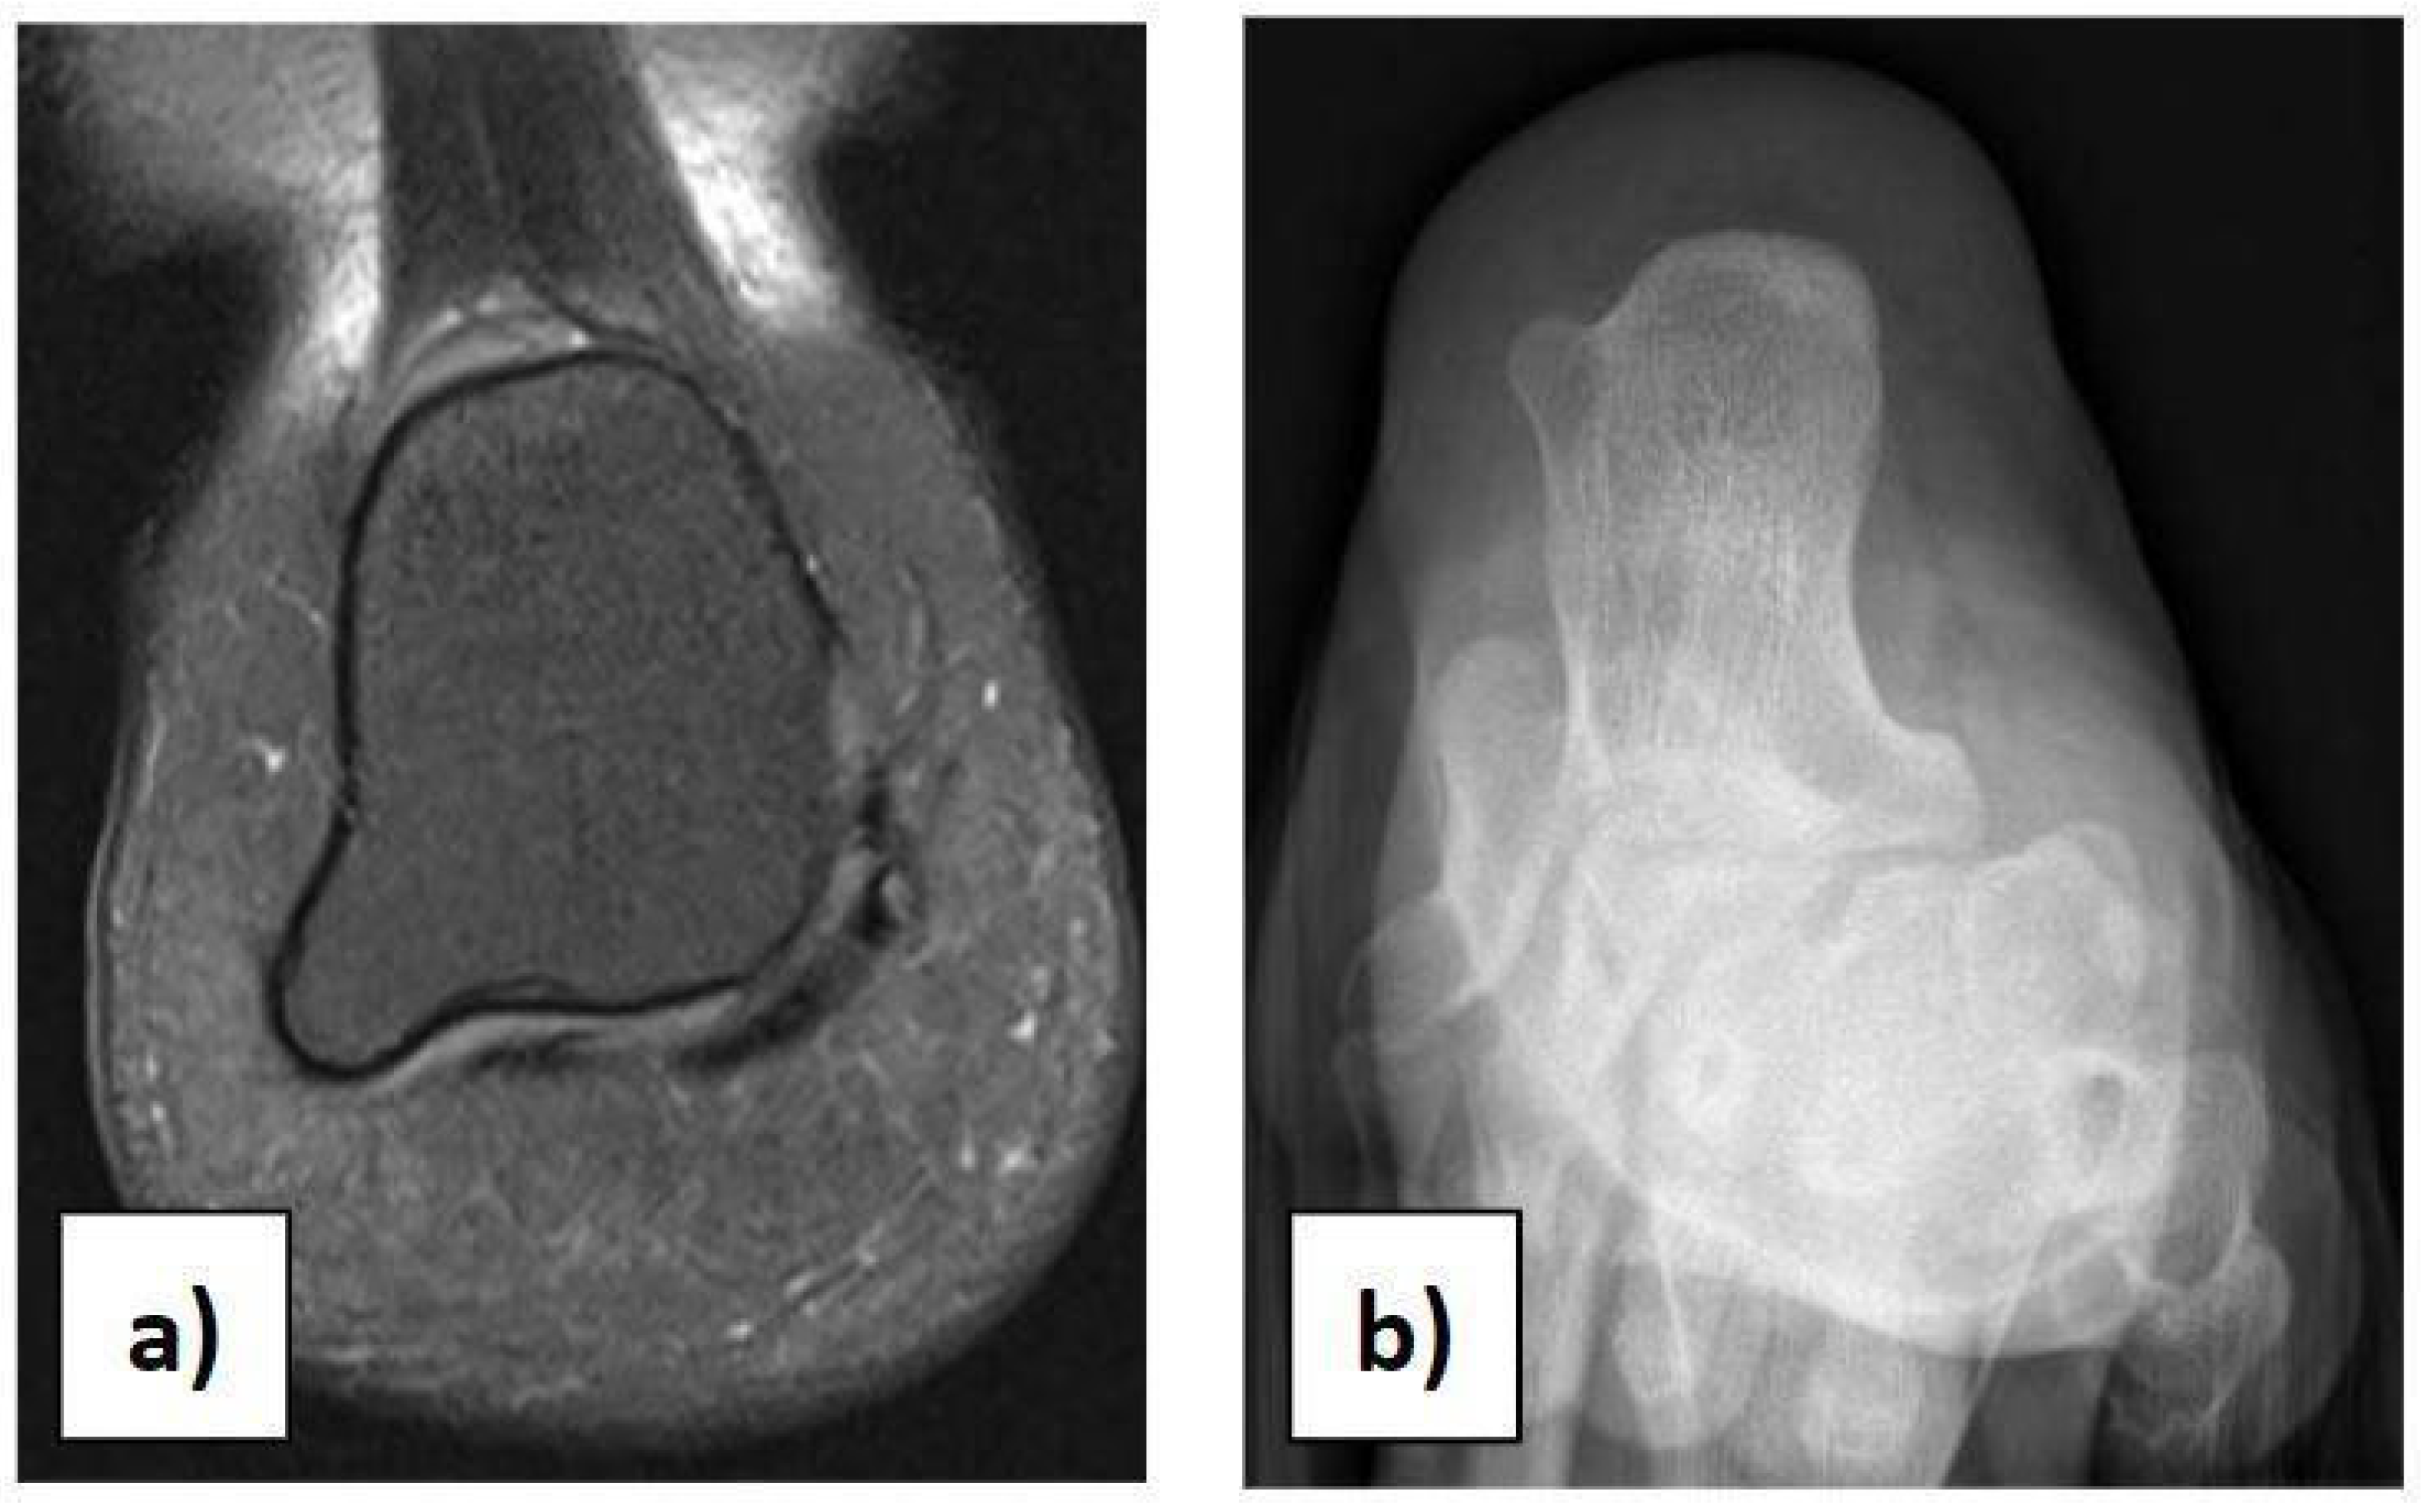

2. Clinical Case